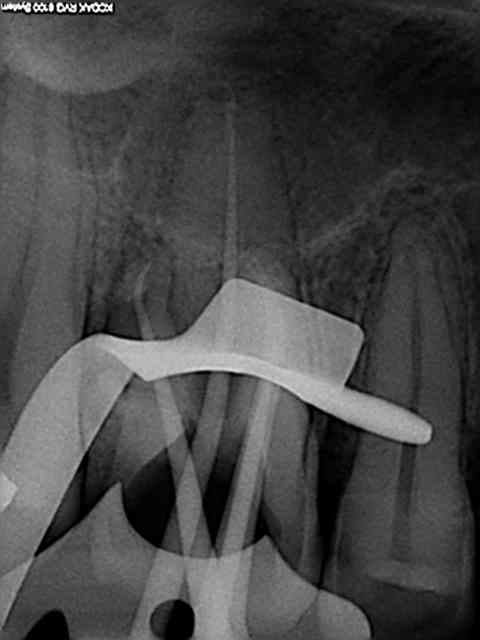

rte sur 16 au r25 un bonheur, le mv2 était imperméable au sx et s1 le r25 n'en a fait qu'une bouchée!

> rte sur 16 au r25 un bonheur, le mv2 était imperméable au sx et s1 le r25 n'en a

> fait qu'une bouchée!

C'est vrai, mais attention quand tu commences à faire des rte au reciproc tu te mets forcément à forcer un peu. La plupart du temps ça marche, et puis parfois ça fait de belles perfos !

Je ne l'utilise plus qu'au niveau apical sur les rte pour débloquer certaines situations.